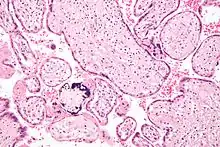

Micrograph of CMV placentitis

Micrograph of CMV placentitis A 3D Power Doppler image of vasculature in 20-week placenta